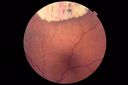

Macular Macroaneurysm with Coats Disease412 views61 year old man with increased leakage from macular macroaneurysm right eyeApr 06, 2019

Macular Macroaneurysm with Coats Disease381 views61 year old man with increased leakage from macular macroaneurysm right eyeApr 06, 2019